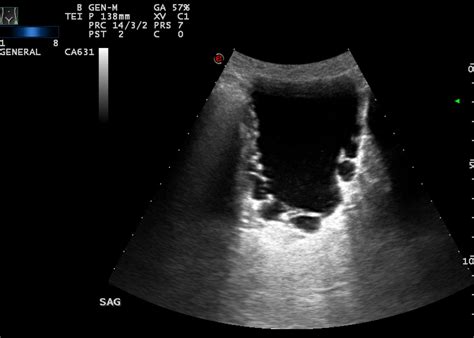

To confirm the presence of Diverticula Of The Urinary Bladder, healthcare professionals rely on a variety of imaging techniques. A thorough diagnostic process ensures that the physician can determine the size, position, and impact of the diverticulum on overall bladder function.

Ultrasound Non-invasive; often used as a first-line assessment tool.